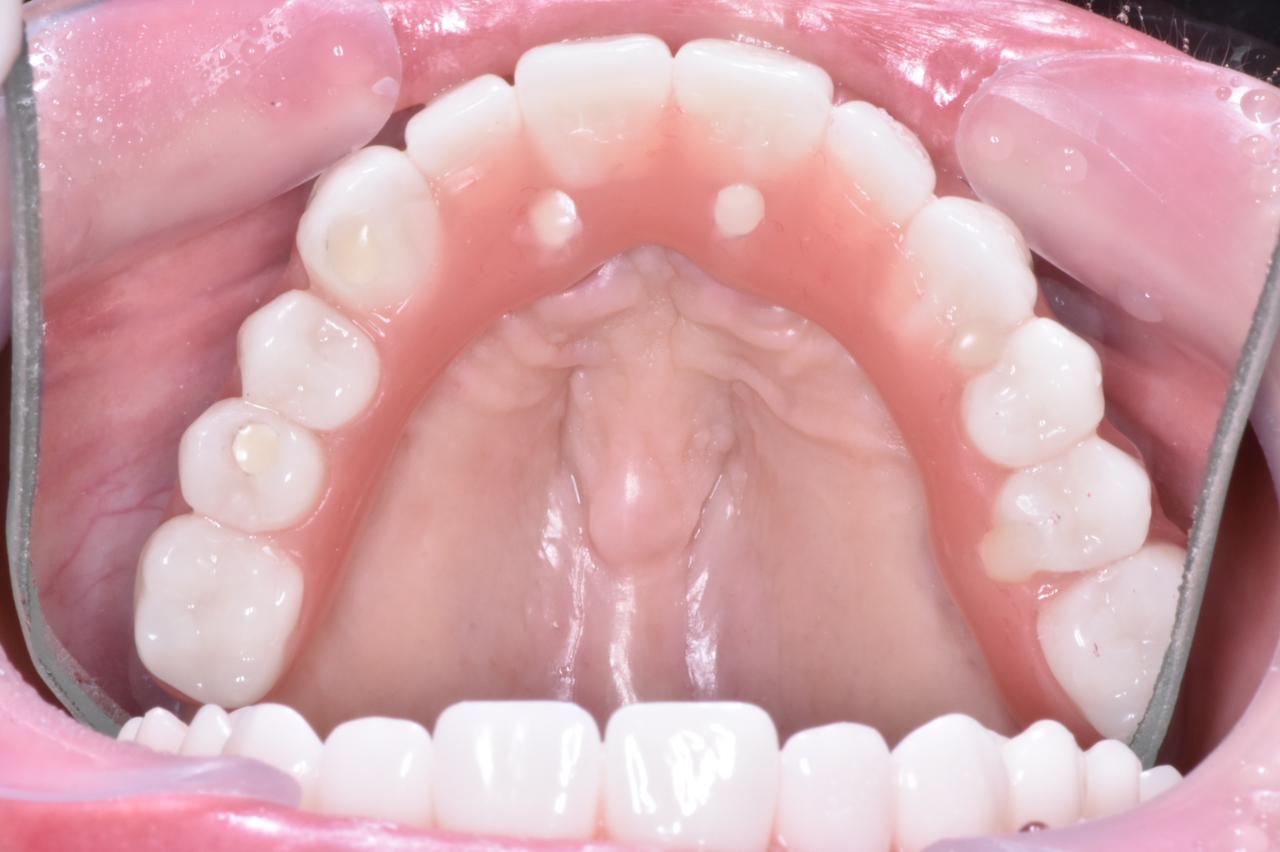

Prótesis híbrida

Son prótesis sin paladar que va fija a unos implantes, por lo tanto no es removible. Es el tratamiento perfecto para pacientes que están cansados de tener prótesis totales, donde no pueden tener buena masticación y degustación de los alimentos.